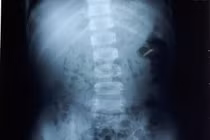

Qua thăm khám, làm siêu âm hệ niệu và X-quang bụng, các bác sĩ khoa Ngoại Thận – Tiết Niệu – Nam Học BVĐK Tỉnh Bắc Giang phát hiện nhiều viên sỏi ở cả hai thận kích thước nhỏ 3mm và có 01 viên sỏi bàng quang kích thước 10mm nằm sát cổ bang quang cản trở đường ra của nước tiểu đặc biệt ở tư thế đứng tiểu. Gia đình cháu L cho biết, rất ngạc nhiên vì nghĩ cháu bé như vậy thì không thể có sỏi thận được.